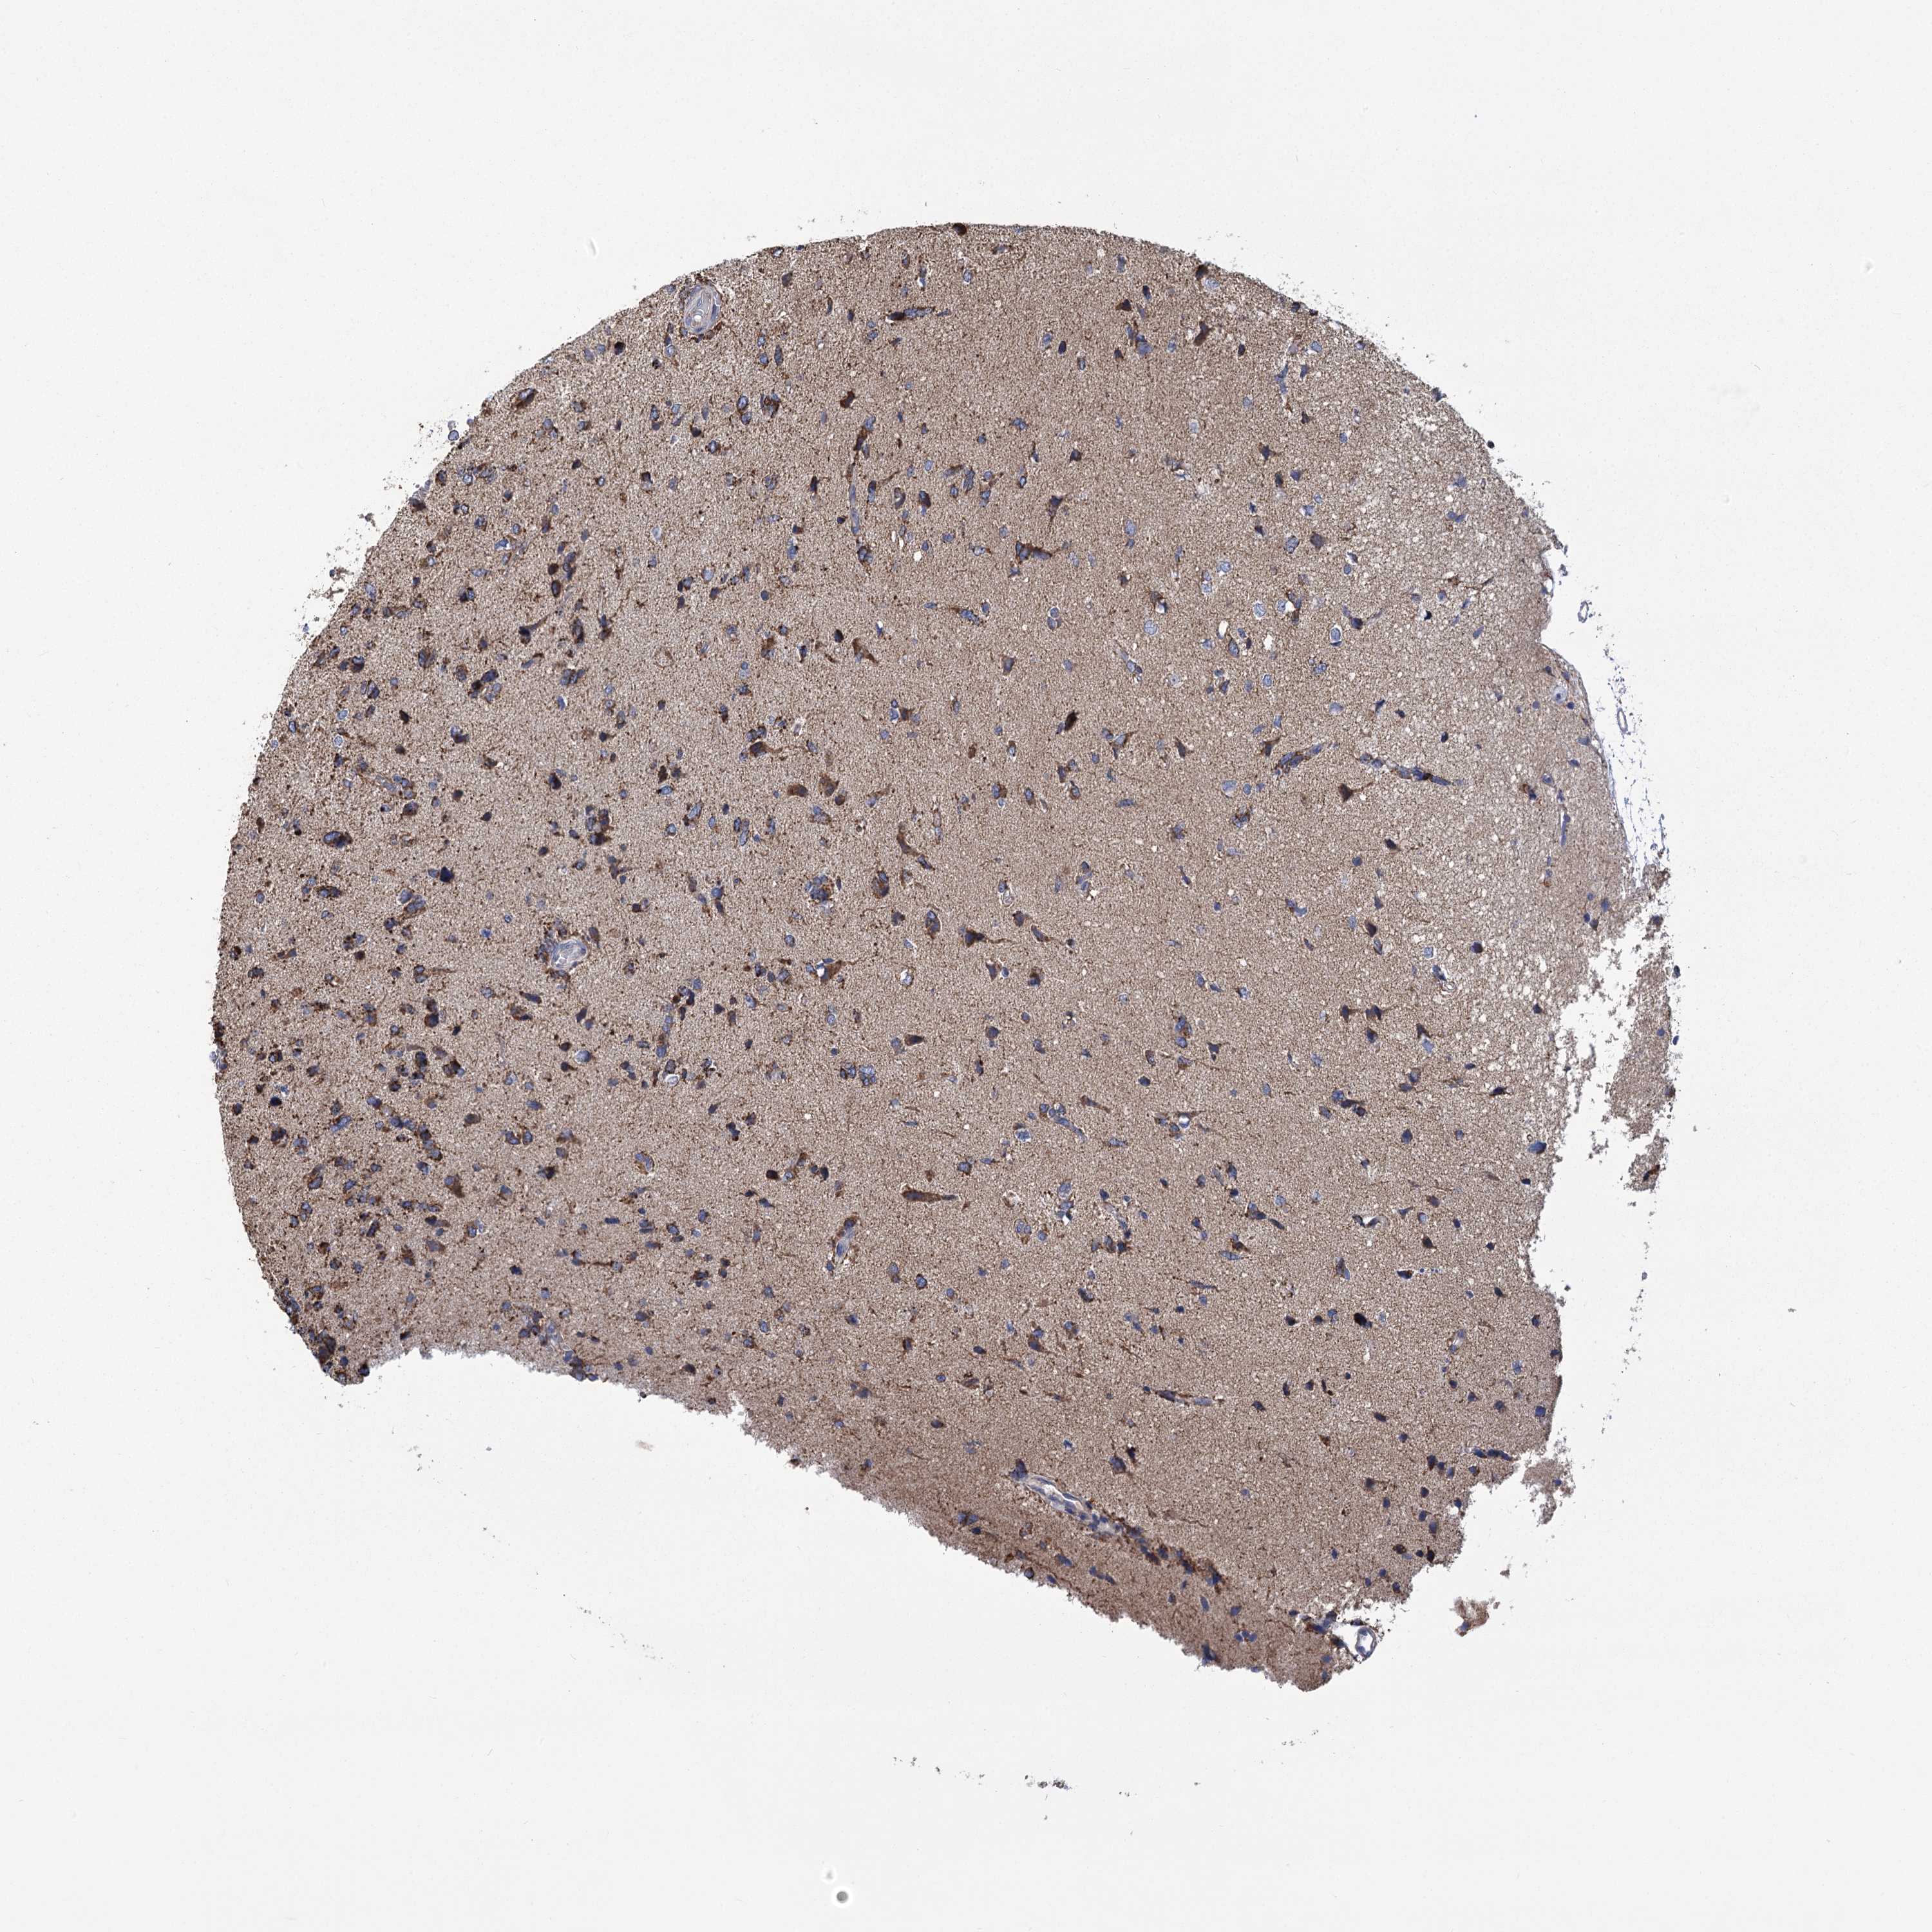

GLIOMA - Protein expressioni

A mouse-over function shows sample information and annotation data. Click on an image to view it in a full screen mode. Samples can be filtered based on level of antibody staining by selecting one or several of the following categories: high, medium, low and not detected. The assay and annotation is described here.

Note that samples used for immunohistochemistry by the Human Protein Atlas do not correspond to samples in the TCGA dataset.

Antibody stainingi

Antibody staining in the annotated cell types in the current human tissue is reported as not detected, low, medium, or high, based on conventional immunohistochemistry profiling in selected tissues. This score is based on the combination of the staining intensity and fraction of stained cells.

Each image is clickable and will lead to virtual microscopy that enables deeper exploration of all samples and also displays staining intensity scores, fraction scores and subcellular localization as well as patient and tissue information for each sample.

Antibody HPA038668

Antibody HPA038669

Glioma, malignant, High grade

Glioma, malignant, Low grade

Glioblastoma, NOS